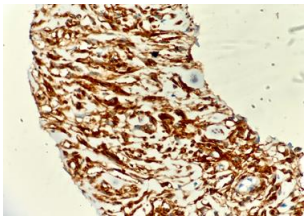

• Histopathology : Histopathology showed diffuse scattered spindle shaped tumor cells displaying nuclear atypia in the form of nuclear enlargement, hyperchromasia and scant eosinophilic cytoplasm. Immunohistochemistry was applied after which GIST was confirmed through immunohistochemical staining which was positive for CD117 (c-KIT), DOG1, SMA(focal), desmin(focal) and CD34. The Ki67 index was 3-5%, indicative of low-grade tumor proliferation.  (Fig 3,4,5,6)

Histopathology fig. 1&2(40x & 400x)- Scanner view showing diffusely scattered spindle shaped tumor cells.

FIG 3, FIG 4

Histopathology fig.3&4(400x)- High power field showing spindle shaped tumor cells showing nuclear atypia in the form of nuclear enlargement, hyperchromasia and scant to moderate eosinophilic cytoplasm.

Fig 5: Immunohistochemistry showing positivity for CD117 (C-KIT).

Fig 6: Immunohistochemistry showing positivity for DOG1. Ki-67 proliferation index was  3-5%.

Figure 3

Figure 4

Figure 5

Figure 6